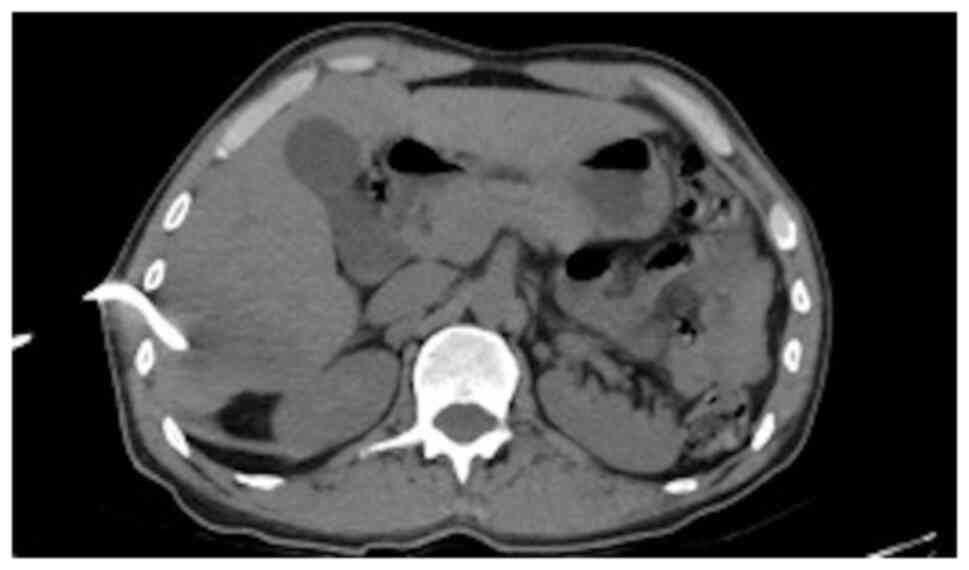

It was decided to perform PoCUS (LOGIQ e, GE Healthcare) following previously established protocols (6). A hypodense intrahepatic image was observed between segments VII and VI, with internal echoes suggestive of a liver abscess (Fig. 1). An ultrasound of the liver and bile ducts performed by a radiologist was requested. A well-defined hypodense lesion between segments VII and VI was confirmed, measuring 81x78x76 mm, with an approximate volume of 253 cc. He presented internal echoes, faint posterior acoustic enhancement and minimal perilesional vascular flow, findings that were associated with the clinical suspicion of liver abscess (Fig. 2). On the same day, radiology and general surgery were consulted. It was decided to perform tomography-guided percutaneous drainage of the liver abscess (IQon Spectral CT, Philips) following formerly recognized protocols (6). A 230 cc drainage was obtained, with no complications (Fig. 3, Fig. 4 and Fig. 5).

Figure 3

Simple abdominal tomography. Evidence of liver injury in segments VI and VII is compatible with an 84x88 mm abscess.